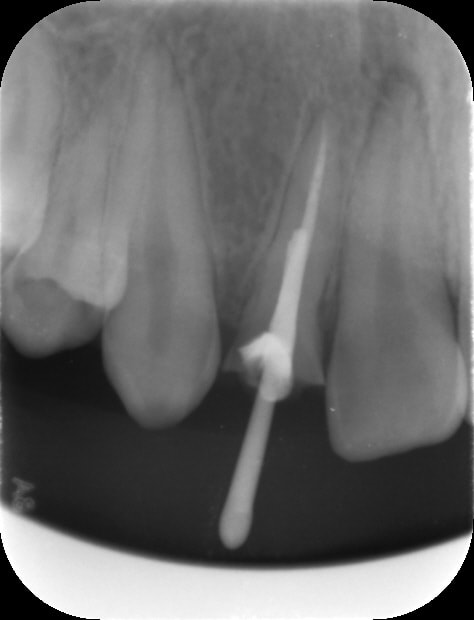

- incisive latérale cassée suite à un gros choc vue en urgence

- 1er RDV : j'ai pas trop de temps en urgence : du coup j'anesthésie , je dépulpe ,je n'obture pas , j'irrigue ET je fais ma préparation pour Inlay core. Je prends ensuite l'empreinte pour l'inlay core

- 2ème RDV : je fais le ttt endo complet puis je désobture la gutta pour poser mon Inlay Core dans la même séance que mon endo et je fais dans la foulée ma couronne provisoire coque polycarbonate de teinte plus claire

par contre regardez voir l'incisive centrale : on dirait qu'elle a dégusté aussi à l'apex

À moins que ça une conséquence du choc ?!

Je vais faire un test au froid sur la centrale ça me paraît louche